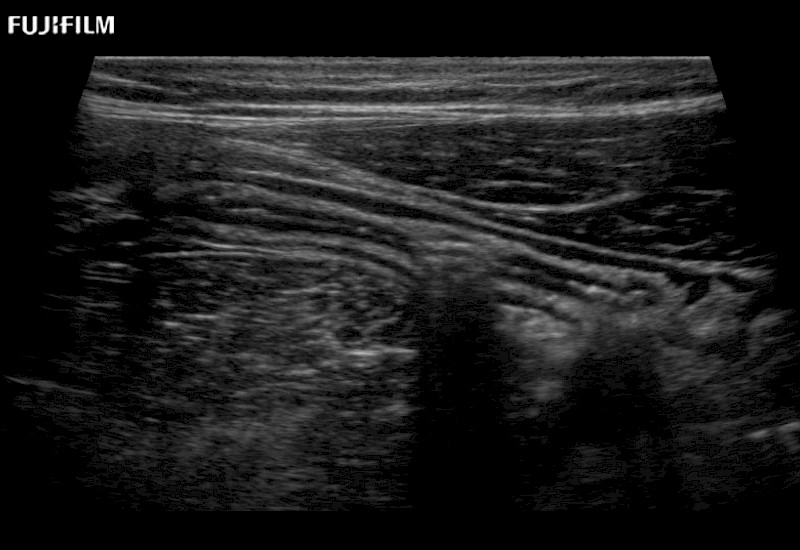

Learn moreFujifilm Healthcare continues to listen to the experts, our neurosurgeons, by developing an ultrasound system specifically designed for the Operating Room.

Guidance is the fundamental purpose for all of our surgical ultrasound technology. Fujifilm Healthcare is committed to designing tools that help neurosurgeons navigate inside the human body and provide the necessary information to immediately make critical surgical decisions.

With the ARIETTA Precision the next level of surgical ultrasound is here.